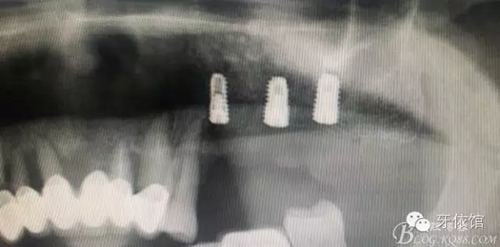

患者男性,62歲,X光片顯示竇底有二維20x15mm囊腫,竇膜內(nèi)無(wú)內(nèi)容物

計(jì)劃:1.外開(kāi)窗2.摘除囊腫3.植骨期植入植體